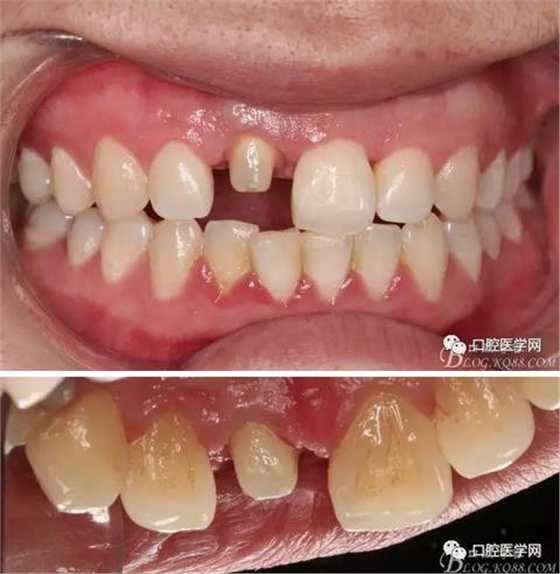

牙冠延長(zhǎng)術(shù)后6周復(fù)診牙齦齦緣形態(tài)恢復(fù)良好,齦乳頭有些欠缺,患者著急永久修復(fù)。

比色

備牙

戴牙